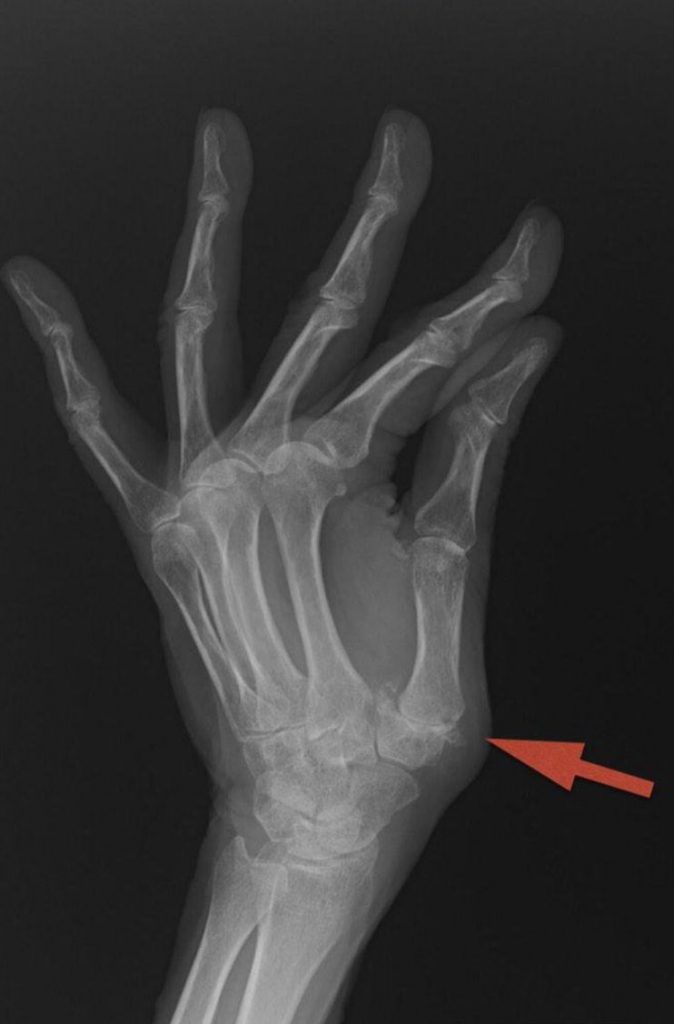

Los pacientes que no responden a tratamiento conservador pueden necesitar cirugía.  Están descritas diferentes técnicas para tratar la Rizartrosis.  Entre las más utilizadas están las prótesis (Figuras 3 y 4), que permiten una recuperación funcional rápida con una muy buena respuesta al dolor.  El Dr. Polo le informará de cuál es la opción más adecuada a su caso.

RIZARTROSIS Figura 4 - Prótesis de articulación TMC por rizartrosis LAT

Figura 4 - Prótesis de articulación TMC por rizartrosis LAT